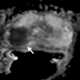

T2-hypointense prostate mass